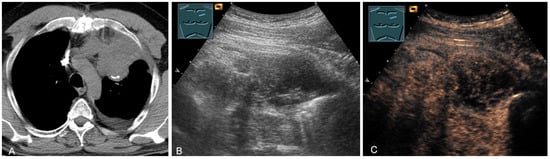

Malignant tumors of the chest wall are characterized by infiltration of tumor tissue into the surrounding structures. On B-mode US, malignant soft tissue tumors usually present as inhomogeneous hypoechoic lesions with anechoic (necrotic) areas or calcifications and often show increased vascularization (Figure 8) [17]. The diagnosis is made histologically.

Figure 8.

Top row: a neuroendocrine tumor on computed tomography (CT) (provided by Prof. Dr. Andreas H. Mahnken, Marburg, Germany) (A), CDS (B), and CEUS (C), here with inhomogeneous enhancement. Bottom row: a plasmocytoma infiltration on CT (D), B-Mode US (E), and CEUS (F), here with homogeneous marked enhancement.